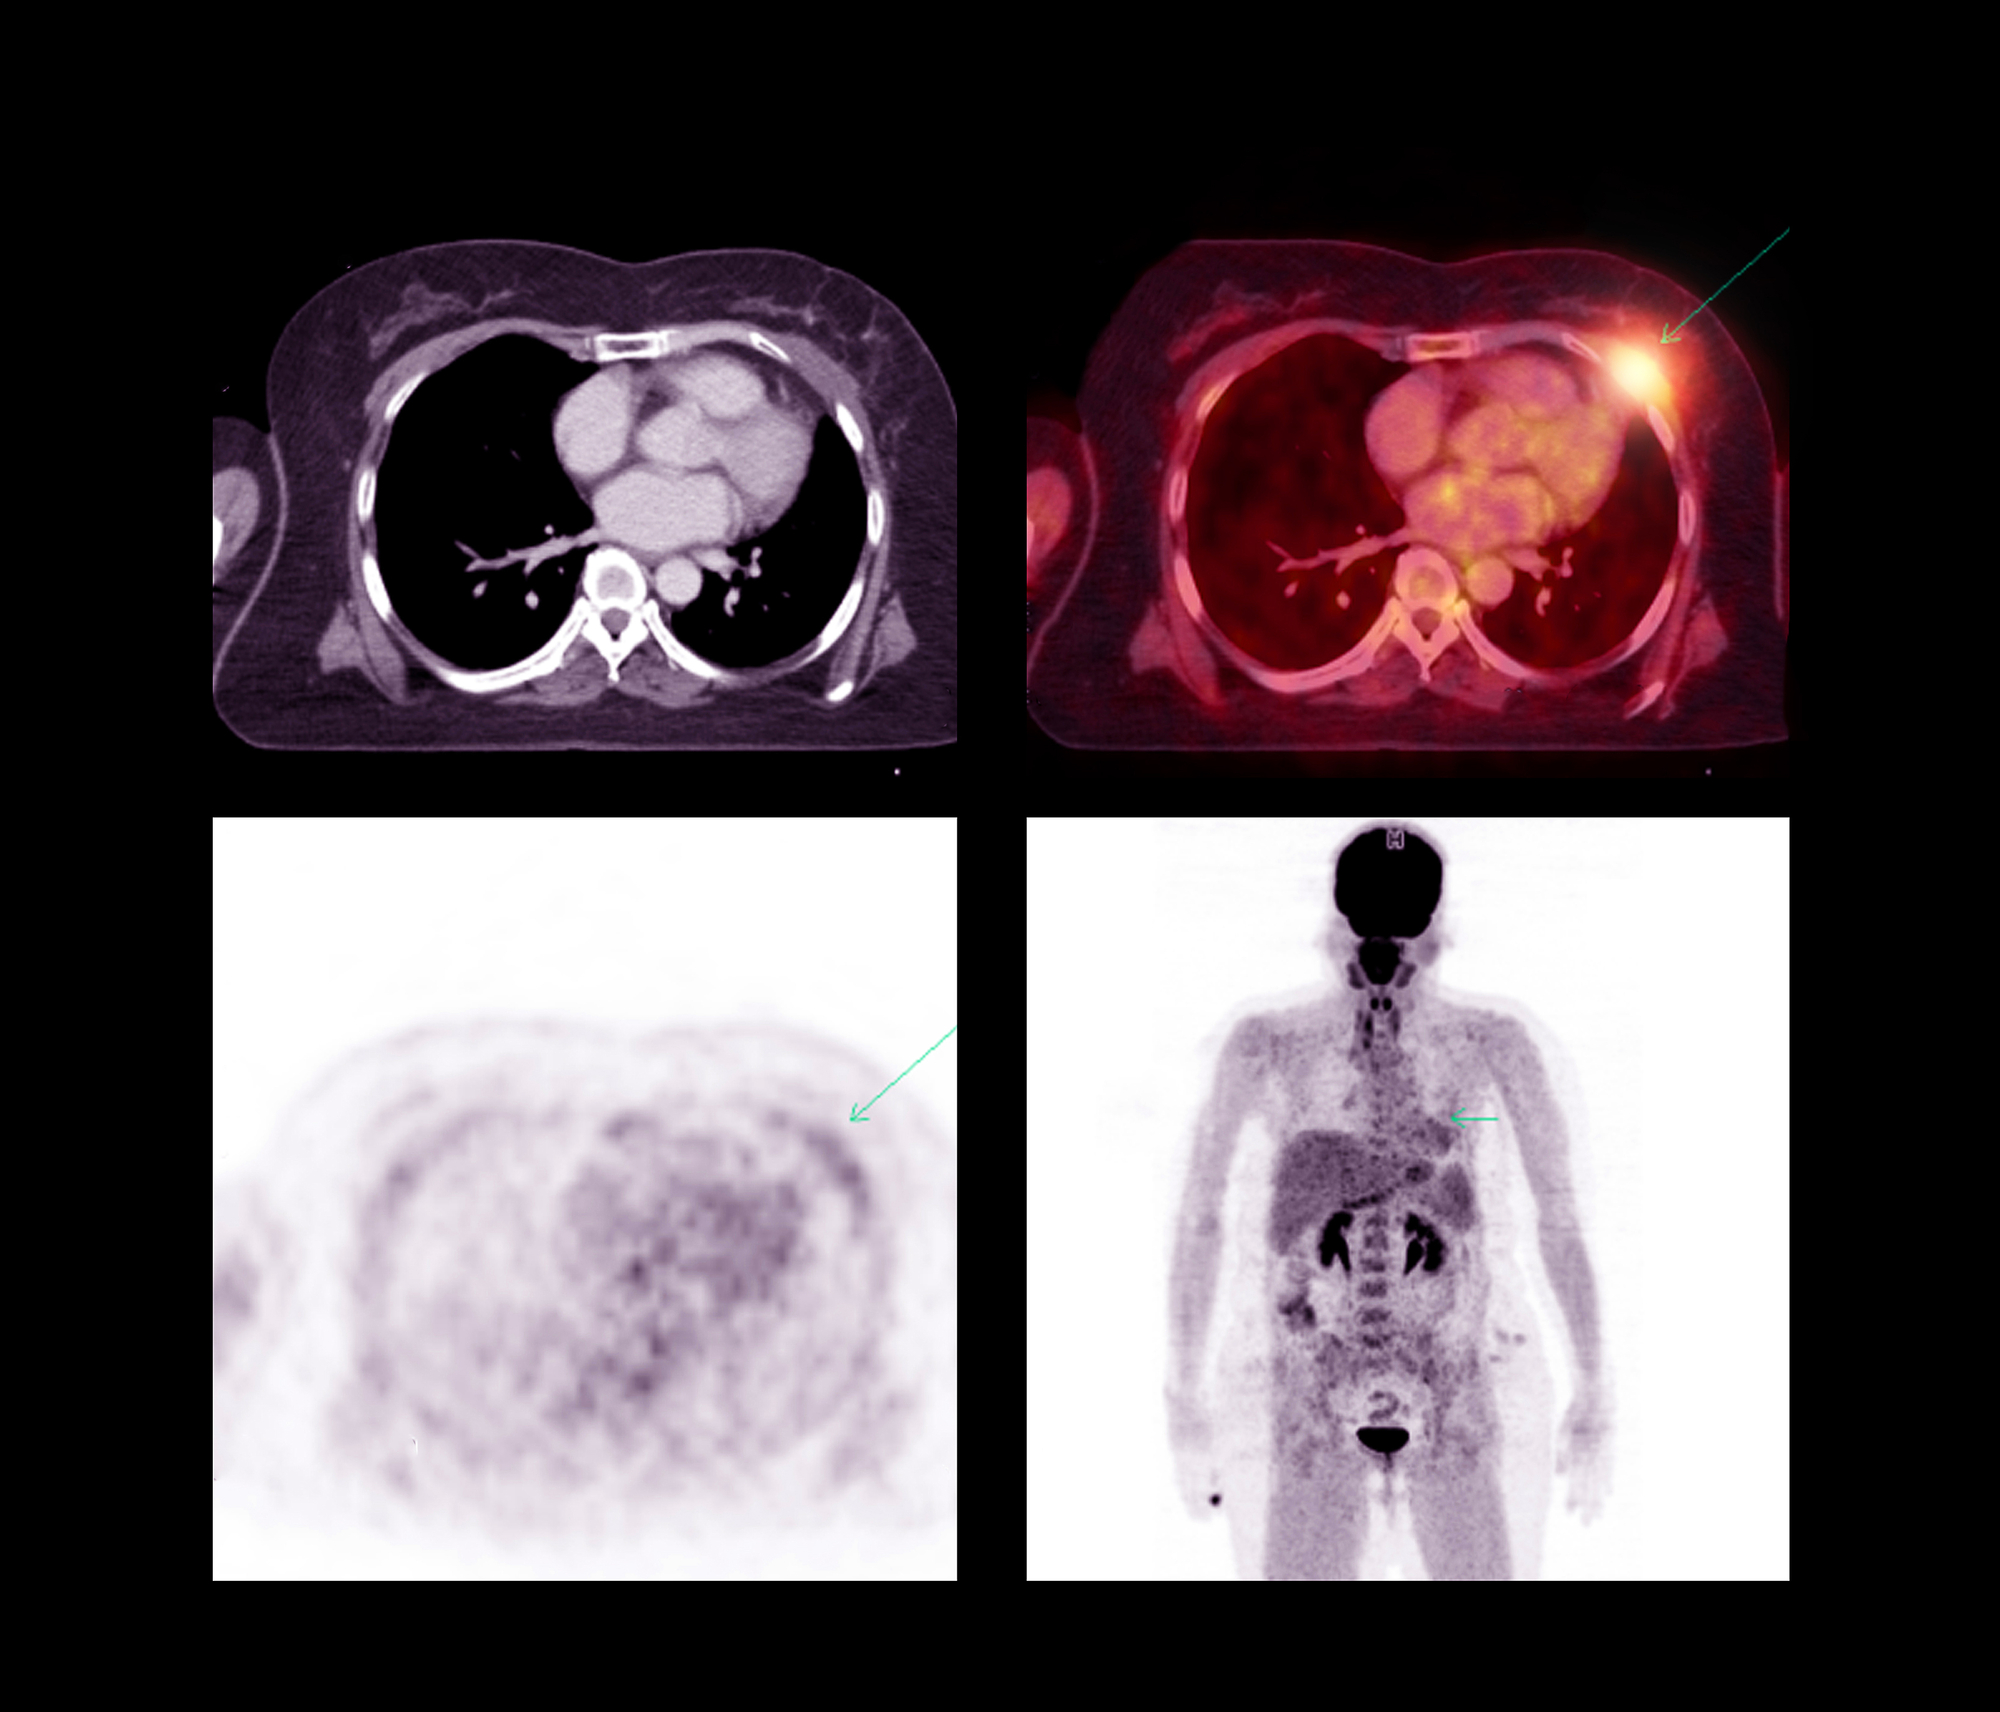

A PET Scan uses a special camera that combines the functions of both positron emission tomography and computed tomography. A positron emission tomography, or PET, is a nuclear medicine imaging test used to measure how well organs and tissues work in your body. A computed tomography scan, also called a CT scan, is an X-ray procedure that uses special X-ray equipment to take clear and detailed images of your body.

PET Scans are beneficial for cancer diagnosis because they can show how aggressive a tumor is and whether it has spread to other parts of the body. Because of this, PET Scans can help diagnose and stage cancer. Doctors also use PET Scans to monitor cancer treatment progress and look for signs of recurrence.